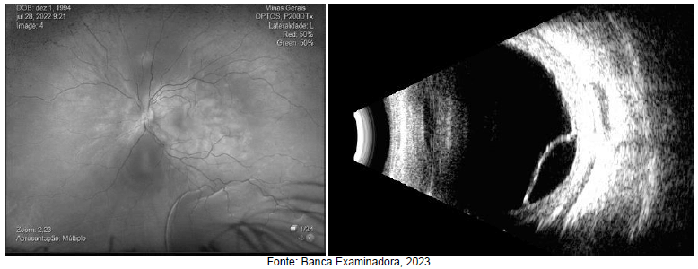

Paciente do sexo feminino, 29 anos, comparece ao serviço de oftalmologia com quadro de baixa acuidade visual e hiperemia no OE h á 6 dias. Nega sintomas associados e relata quadro viral h á cerca de 3 semanas. Paciente nega comorbidades ou uso de medicamentos. Ao exame, apresenta acuidade visual no OE <20/ h iperemia conjuntival e reação de câmara anterior. OD sem alterações ao exame. Imagens da fundoscopia e ultrassom da paciente nas figuras abaixo.

Qual o provável diagnóstico?